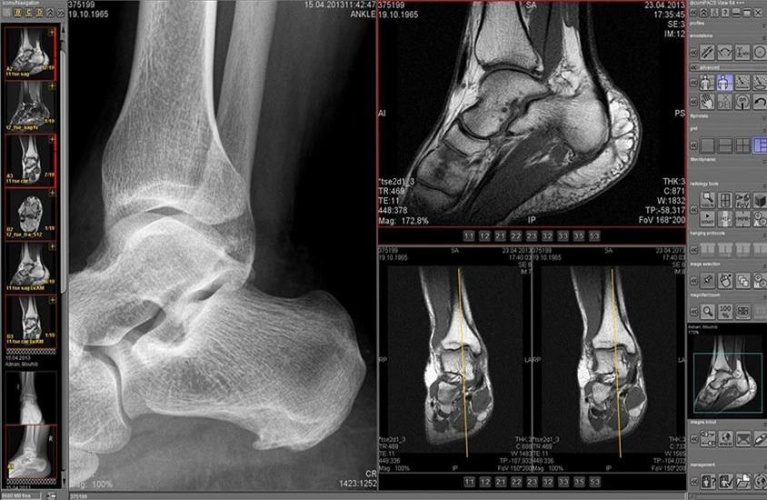

این موارد شما را برای مرحله بعدی در این سفر آماده کردهاند و این مرحله به بررسی نحوه کارکرد دایکام با تصاویر پزشکی میپردازد. بدون شک، تصاویر ویژگیهای شناخته شدهای دارند که از جمله آنها میتوان به عرض، طول و تعداد پیکسل اشاره کرد که میتوان آنها را در دیکشنری داده دایکام پیدا نمود و همانطور که پیشتر نیز یاد گرفتید، دایکام آنها را با استفاده از واقعیت مجازی ضمنی یا صریح رمزگذاری میکند. اما جالبترین ویژگی تصویر، همان خود تصویر است که توالی مقادیر پیکسلی میباشد و دایکام آن را در تگ داده پیکسلی استاندارد (vFE0, 0010)با استفاده از OB (برای پیکسلهای یک بایتی) یا OW (برای نمونه پیکسلهای دو بایتی) رمزگذاری میکند.

دایکام از گستره وسیعی از فرمتهای تصویری برای ذخیره این پیکسلها (vFE0, 0010)ستفاده میکند. فرمتها را میتوان در دو دسته طبقهبندی نمود: